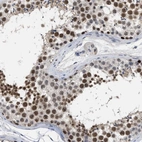

Immunohistochemical staining of human testis shows strong nuclear positivity in cells of seminiferus ducts.